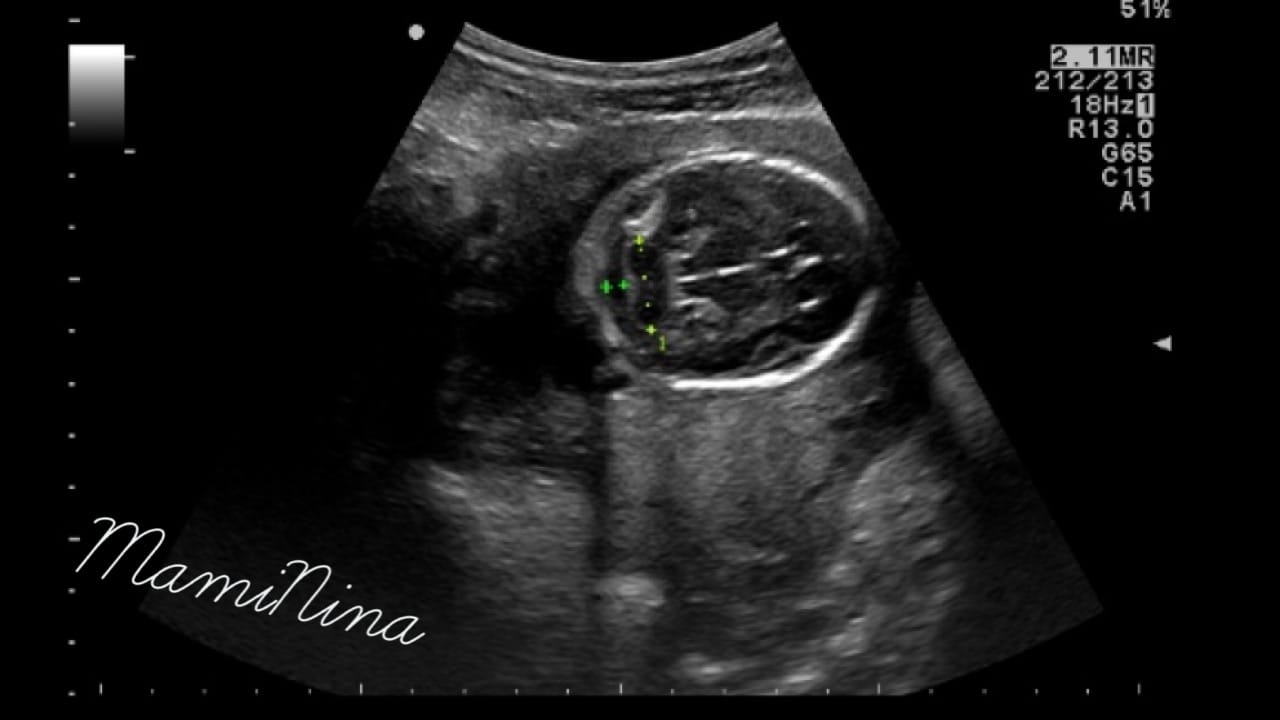

Zdravnica je izmerila dolžino maternice in pričela z ultrazvočnim pregledom. Za začetek z odličnim pogledom na utripajoči srček in njegove štiri prekate. Skozi pregled smo pregledali prav vse od začetka do konca, rokice, nogice, hrbtenico, rebra, usta, oči, res, ni da ni. Izredno se je potrudila in nama z možem pokazala vse, kar je le lahko. Pogledali smo tudi, kako je plod ravno v trenutku, ko smo opazovali profil obrazka nekaj prav na veliko pogoltnil, kar je bilo res prav zanimivo.

Glede na mere je trenutna teža ocenjena na 340 g, kar je popolnoma v mejah normale, s temi podatki pa se za nekaj dni premakne tudi predvideni datum poroda, ampak uradno v knjižici ostaja zapisan datum 2.7.2017 (prav noro lepe številke, ampak saj vemo, da se izredno malo otrok dejansko rodi na PDP).

(na dodanih slikah lahko vidite glavico, nogico in profil obrazka naše princeske)